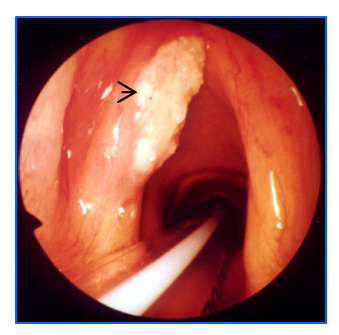

正常电子喉镜图片,箭头所示为声带

通常在耳鼻咽喉科门诊行电子喉镜检查可发现病变。电子喉镜能深入喉部,清晰地呈现病变部位的形态、大小和位置,如果需要明确病变性质则需行手术切除部分病变组织进行病理检查,这是确诊喉癌的“金标准”。同时需要进一步行喉部的CT或MRI扫描,目的是为了解喉癌的大小和准确位置及范围。如果有条件还可以行PET-CT 检查,它可以从代谢层面评估肿瘤的活性,发现潜在的转移病灶,对肿瘤的分期和预后判断具有重要价值。结合喉部肿瘤大小,颈部淋巴结转移情况及全身转移情况进行分期,越早治疗,治疗效果越好。晚期效果较差而且保留喉的可能性很小。